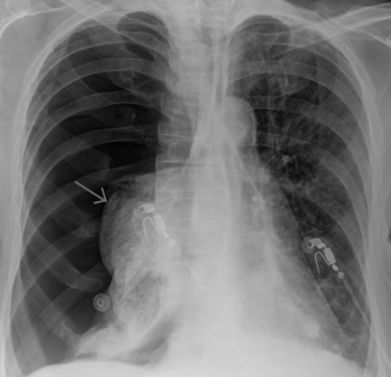

- рентгенографию органов грудной клетки;

- КТ;

- рентгенографию грудной клетки;

- компьютерную томографию;